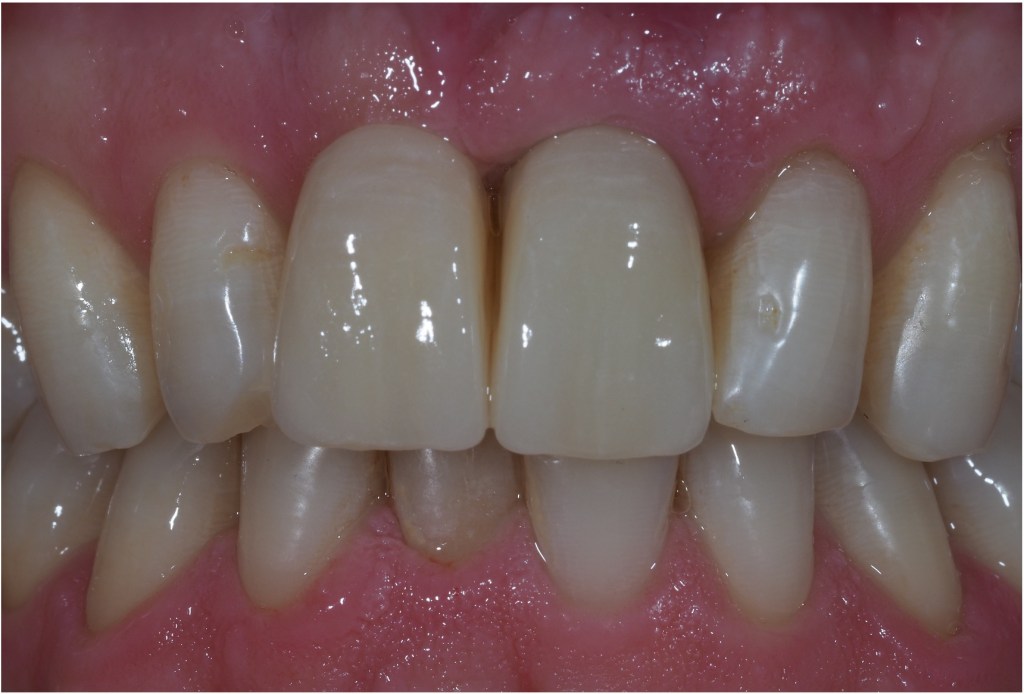

Single implant crowns are an excellent way to replace missing teeth. They do not damage the neighbouring teeth and last for a long period of time. These are usually screw retained to allow repair/replacement if there are any maintenance issues.